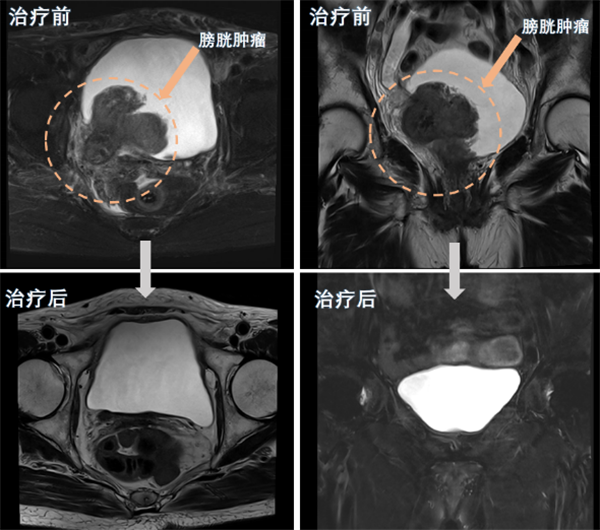

近日,皇冠足球投注网 (简称皇冠足球网 )泌尿外科团队为一名80岁高龄的巨大膀胱肿瘤患者实施了经尿道膀胱肿瘤剜除术及术后精准综合治疗,成功保住了该患者的膀胱。经过四个周期的综合治疗后,患者膀胱恢复完好,未见肿瘤复发。该手术的成功,标志着皇冠足球投注网 泌尿外科在膀胱癌诊治和保膀胱治疗技术方面取得了新突破。半年前,80岁的苏奶奶(化名)因反复无痛性肉眼血尿在当地医院就诊,经...